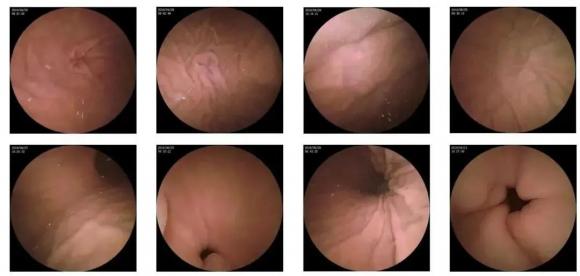

10—15分鐘即可完成賁門、胃底、胃體、胃角、胃竇、幽門等解剖部位觀察,讓胃部檢查更高效。更為重要的是,檢查全程不痛、沒創、無麻醉,避免了傳統插管胃鏡帶來的生理痛苦。

膠囊機器人的專利三鏡片鏡頭,可深入觀察0.04毫米微小單位,每秒可拍高達4張高清醫學照片。

任何細微的胃部病變,如胃潰瘍、胃出血、息肉等都無所遁形,盡在磁控膠囊式內窺鏡系統的掌握之中。